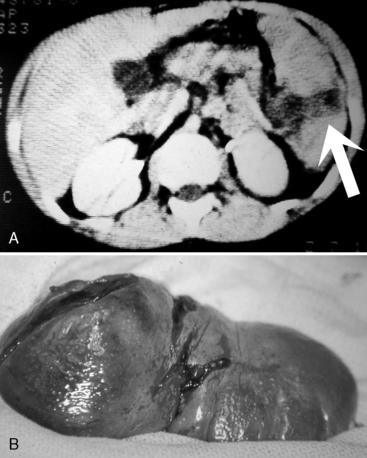

Pulmonary Contusion

A pulmonary contusion is a bruise on the lung resulting from lung parenchymal injury. Although a pulmonary contusion can be asymptomatic and diagnosed only on CT scan, it can cause respiratory compromise following major blunt chest trauma.13,44 A significant pulmonary contusion will cause hypoxemia, and opacification is visible on a chest radiograph or CT scan (see Figs. 19-3, B and 19-4).

image

Fig. 19-4 Pulmonary contusion on chest radiograph and computed tomography (CT) scan. A, Chest radiograph. Note the increased opacification in the patient’s right lower lung fields (arrows). Note the absence of rib fractures. B, CT scan from the same patient demonstrating opacification (white contusion is visible in the dark air density) of the right lower lung. The trachea is not visible in mediastinum, so opacification is below the area of bifurcation of the trachea into bronchi. This CT view is shot from below the area of contusion with a view in the cephalad direction. The patient’s right chest appears on the left side of this image, and the patient’s left chest is visible on the right side of this image. The front of the patient is the top of this image, and the patient’s back is at the bottom of this image; thus, the patient’s heart is anterior (visible as a white oval) and vertebral column is posterior.

An associated hemothorax typically suggests the presence of a more severe lung injury. Treatment includes supplementary oxygen and may require positive-pressure ventilation with oxygen support and positive end-expiratory pressure.